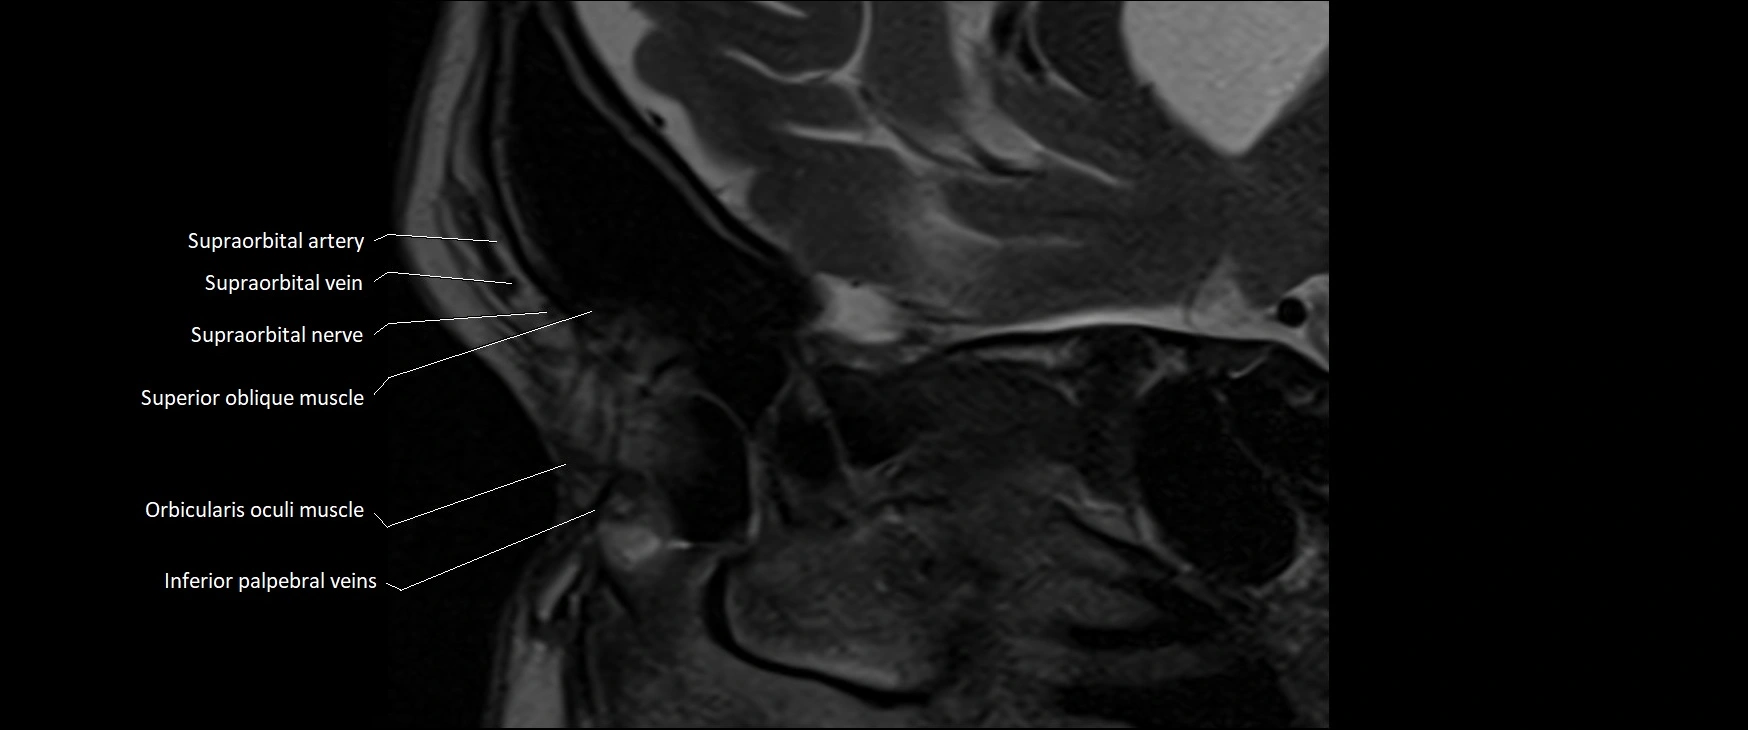

- Orbicularis oculi muscle

- Superior oblique muscle

- Supraorbital artery

- Supraorbital nerve

- Supraorbital vein